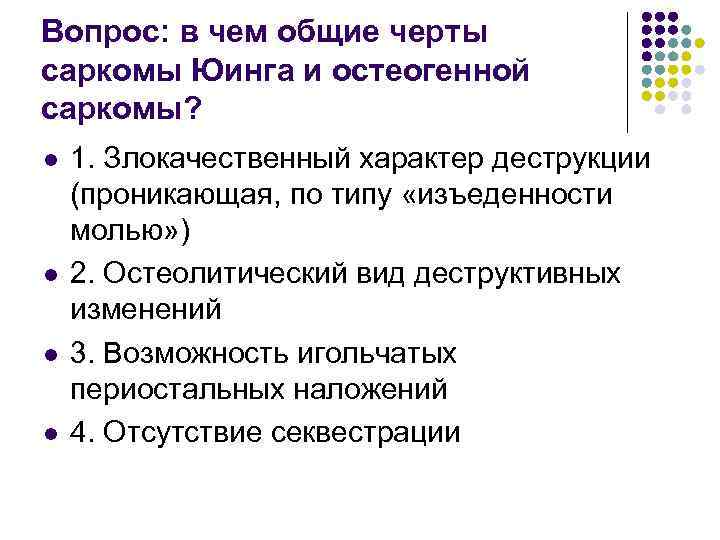

Вопрос: в чем общие черты саркомы Юинга и остеогенной саркомы? l l 1. Злокачественный характер деструкции (проникающая, по типу «изъеденности молью» ) 2. Остеолитический вид деструктивных изменений 3. Возможность игольчатых периостальных наложений 4. Отсутствие секвестрации

Вопрос: в чем общие черты саркомы Юинга и остеогенной саркомы? l l 1. Злокачественный характер деструкции (проникающая, по типу «изъеденности молью» ) 2. Остеолитический вид деструктивных изменений 3. Возможность игольчатых периостальных наложений 4. Отсутствие секвестрации

Ответ: l Все вышеперечисленное

Ответ: l Все вышеперечисленное